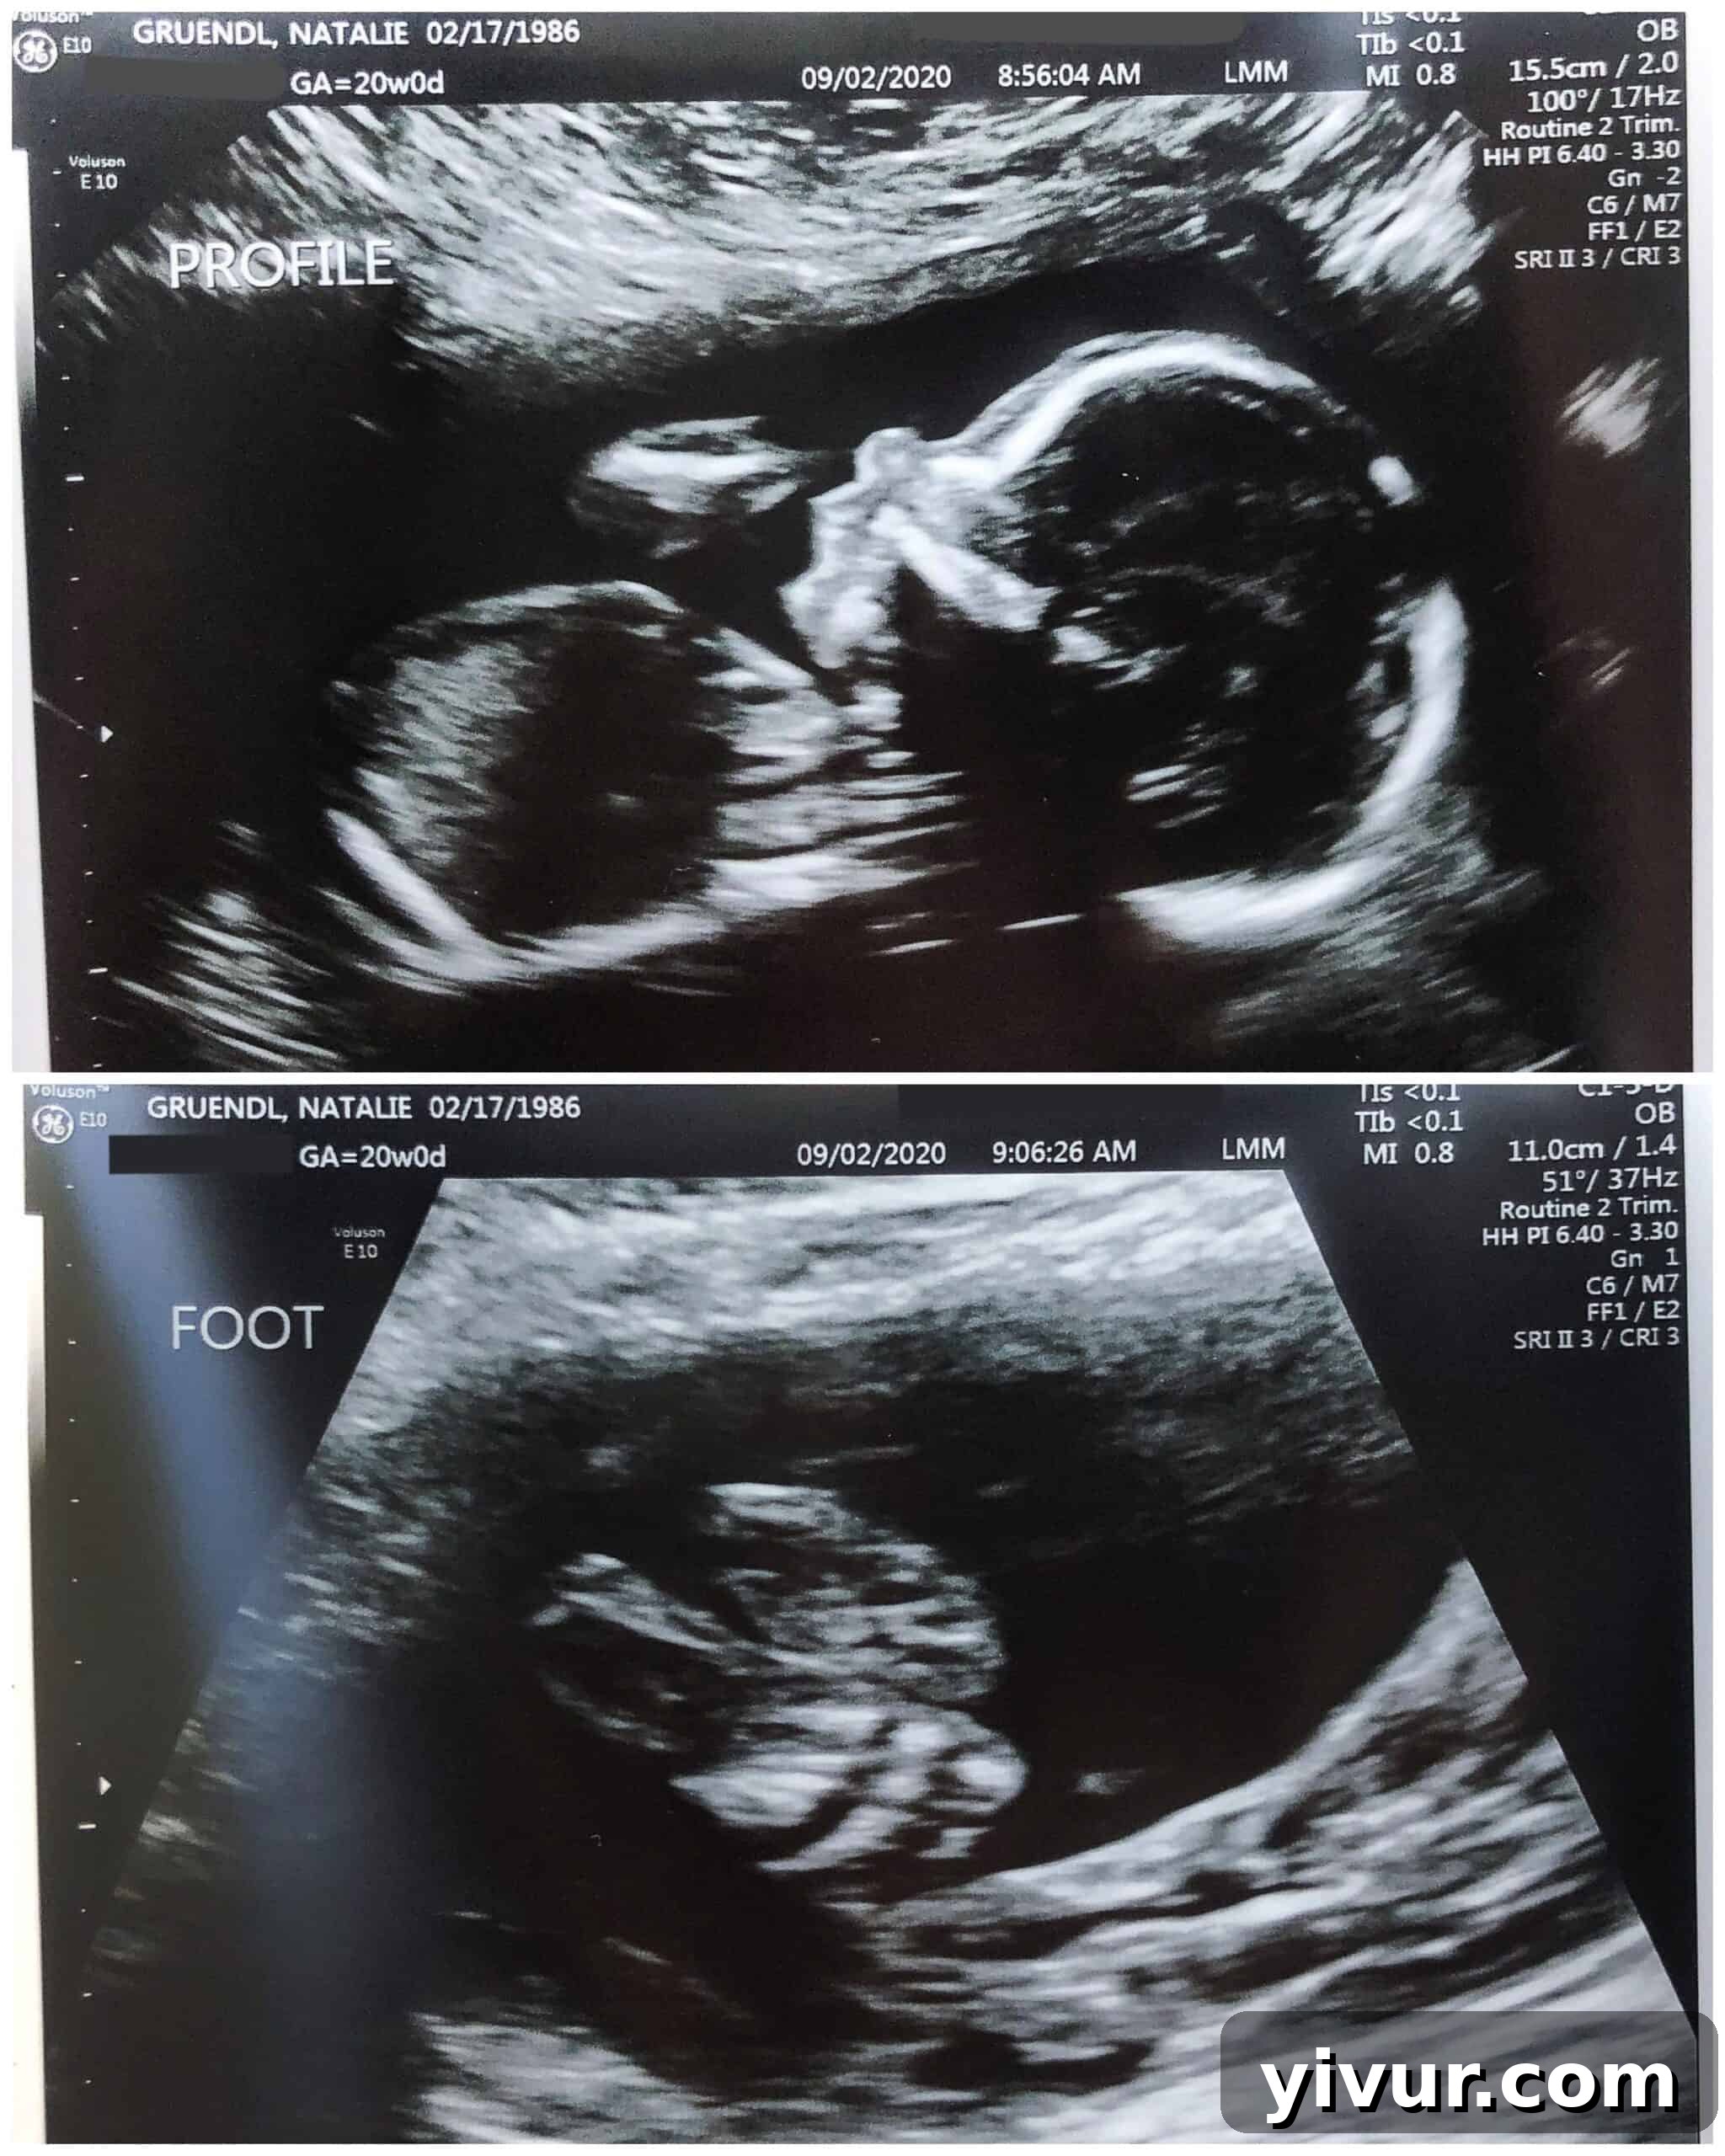

I’m thrilled to share that I’m officially 20 weeks along, marking the incredible halfway point to meeting our newest little boy! This milestone brings with it a wave of excitement and immense gratitude, especially after reaching a significant point in our pregnancy journey just yesterday: our 20-week ultrasound scan.

The news we received was truly the best any expectant parent could hope for: our baby boy is healthy! This affirmation is something we cherish deeply, perhaps even more so because our first son was born with clubfeet. That experience taught us the profound anxiety that can accompany a 20-week scan, and the overwhelming terror of leaving with concerning news. However, it also showed us our strength as a family; our oldest son has overcome his challenges, proving that we are capable of navigating difficult situations. It’s a powerful reminder of how truly blessed we are when we receive the wonderful news that our baby is healthy and thriving.

We’re particularly relieved that our newest addition doesn’t have clubfeet, a condition we faced a much higher risk for given our family history. Knowing he’ll arrive ready to go, without the immediate need for casting and surgeries, is a huge weight lifted. It means we can focus purely on welcoming him into the world with open arms and hearts full of joy. What a wonderful blessing!

Just look at his adorable little profile and tiny feet in these ultrasound images!